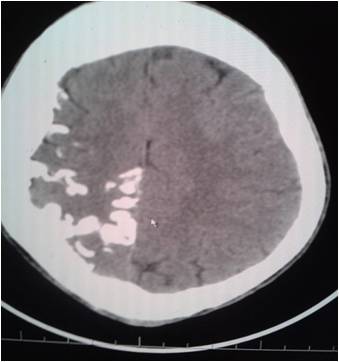

Home » Tram Track Sturge Weber Syndrome Radiology » Tram Track Sturge Weber Syndrome Radiology

Tram Track Sturge Weber Syndrome Radiology